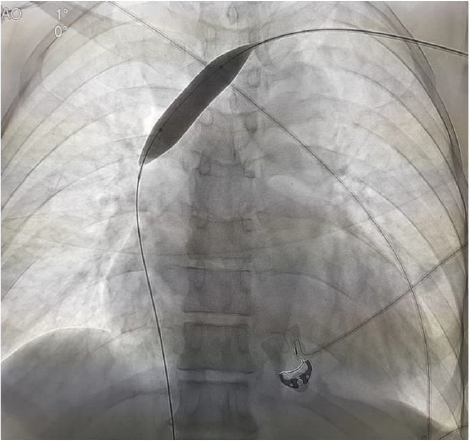

If right IJV is thrombosed, then IR accesses right External Jugular vein (EJV). If right side neck veins are thrombosed, then IR accesses left side neck veins: IJV or EJV (Figure 2). These tunnelled CVC are usually of size 14.5 French, with length 19, 23 or 27 cm, depending on patient’s height and from which side, neck vein is to be accessed. The cuff of tunnelled CVC is believed to prevent transmission of infection and also helps in securing CVC. If properly taken care of, then these tunnelled CVC can be used for 6-12 months. IR helps in managing these tunelled CVC, if flow rate is slow, by repositioning these CVC (Figure 3). IR have important role to play in managing AVF with slow flow rates. Most of times, stenosis is seen in these AVF, near anastomotic site. These juxta anastomotic AVF can be managed by IR by Percutaneous Transluminal Angioplasty (PTA), using appropriate size balloon. Some AVF show aneurysmal formation on venous side and these aneurysms can be managed successfully by IR (Figure 4). Sometimes, steal syndrome can be seen in AVF, due to reversal of flow in artery distal to anastomotic site. In case of steal syndrome, IR can block venous side using coils, in case of side to end AVF. This will increase flow rate in distal artery and reduce flow in fistula. In case of side-to-side AVF with steal syndrome, IR can successfully divert blood flow towards distal artery, by blocking collateral draining vein, distal to side-to-side anastomosis (Figure 5). If there is evidence of central vein stenosis, then IR can do PTA of central vein (Figure 6). If there is evidence of elastic recoil, with residual stenosis more than 30%, then IR can manage central vein stenosis by using metallic stent (Figure 7). Herein, it is important to stress upon Doppler and Spectral waveform, which helps IR to manage these dialysis fistula and graft [3-5]. In mature fistula and graft, inflow artery shows monophasic flow, with raised Peak systolic velocity (PSV) and End Diastolic velocity (EDV), with spectral broadening (Figure 8). In artery distal to anastomotic site, biphasic or triphasic waveform may be seen. On venous side, spectral waveform shows monophasic flow with turbulent arterial waveform (Figure 9).

Figure 7:

A. and

B. Metallic stenting left brachiocephalic vein.

C. Post-venoplasty image shows free venous flow of contrast in left brachiocephalic vein.